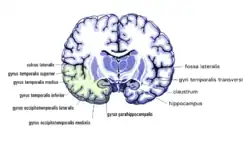

Frontalschnitt

Frontalschnitt -